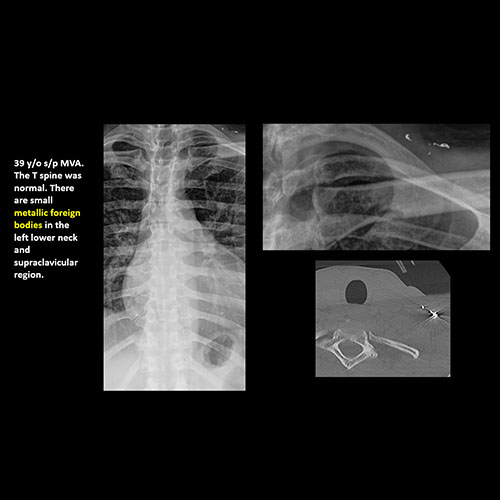

There is abnormality of the soft tissues and bones of the included neck other than from degenerative change. [Yes/No]

There is abnormality of the soft tissues and included bones of the upper extremities, clavicles, and sternum other than from degenerative change. [Yes/No]

There is a foreign body or there are post surgical changes of the bones or soft tissues of the included neck, thorax, or abdomen. [Yes/No]